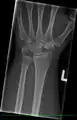

1. Stage I Normal radiograph (possible lunate fracture).

2. Stage II Sclerosis of the lunate without collapse. (Portions of the lunate begin to deteriorate. This shows as a white blemish on x-rays.)

3. Stage IIIA Lunate collapse and fragmentation, in addition to proximal migration of the capitate.

4. Stage IIIB Lunate collapse and fragmentation, in addition to proximal migration of the capitate. In addition there is fixed flexion deformity of the scaphoid.

5. Stage IV Changes up to and including fragmentation, with radiocarpal and midcarpal arthritic changes.